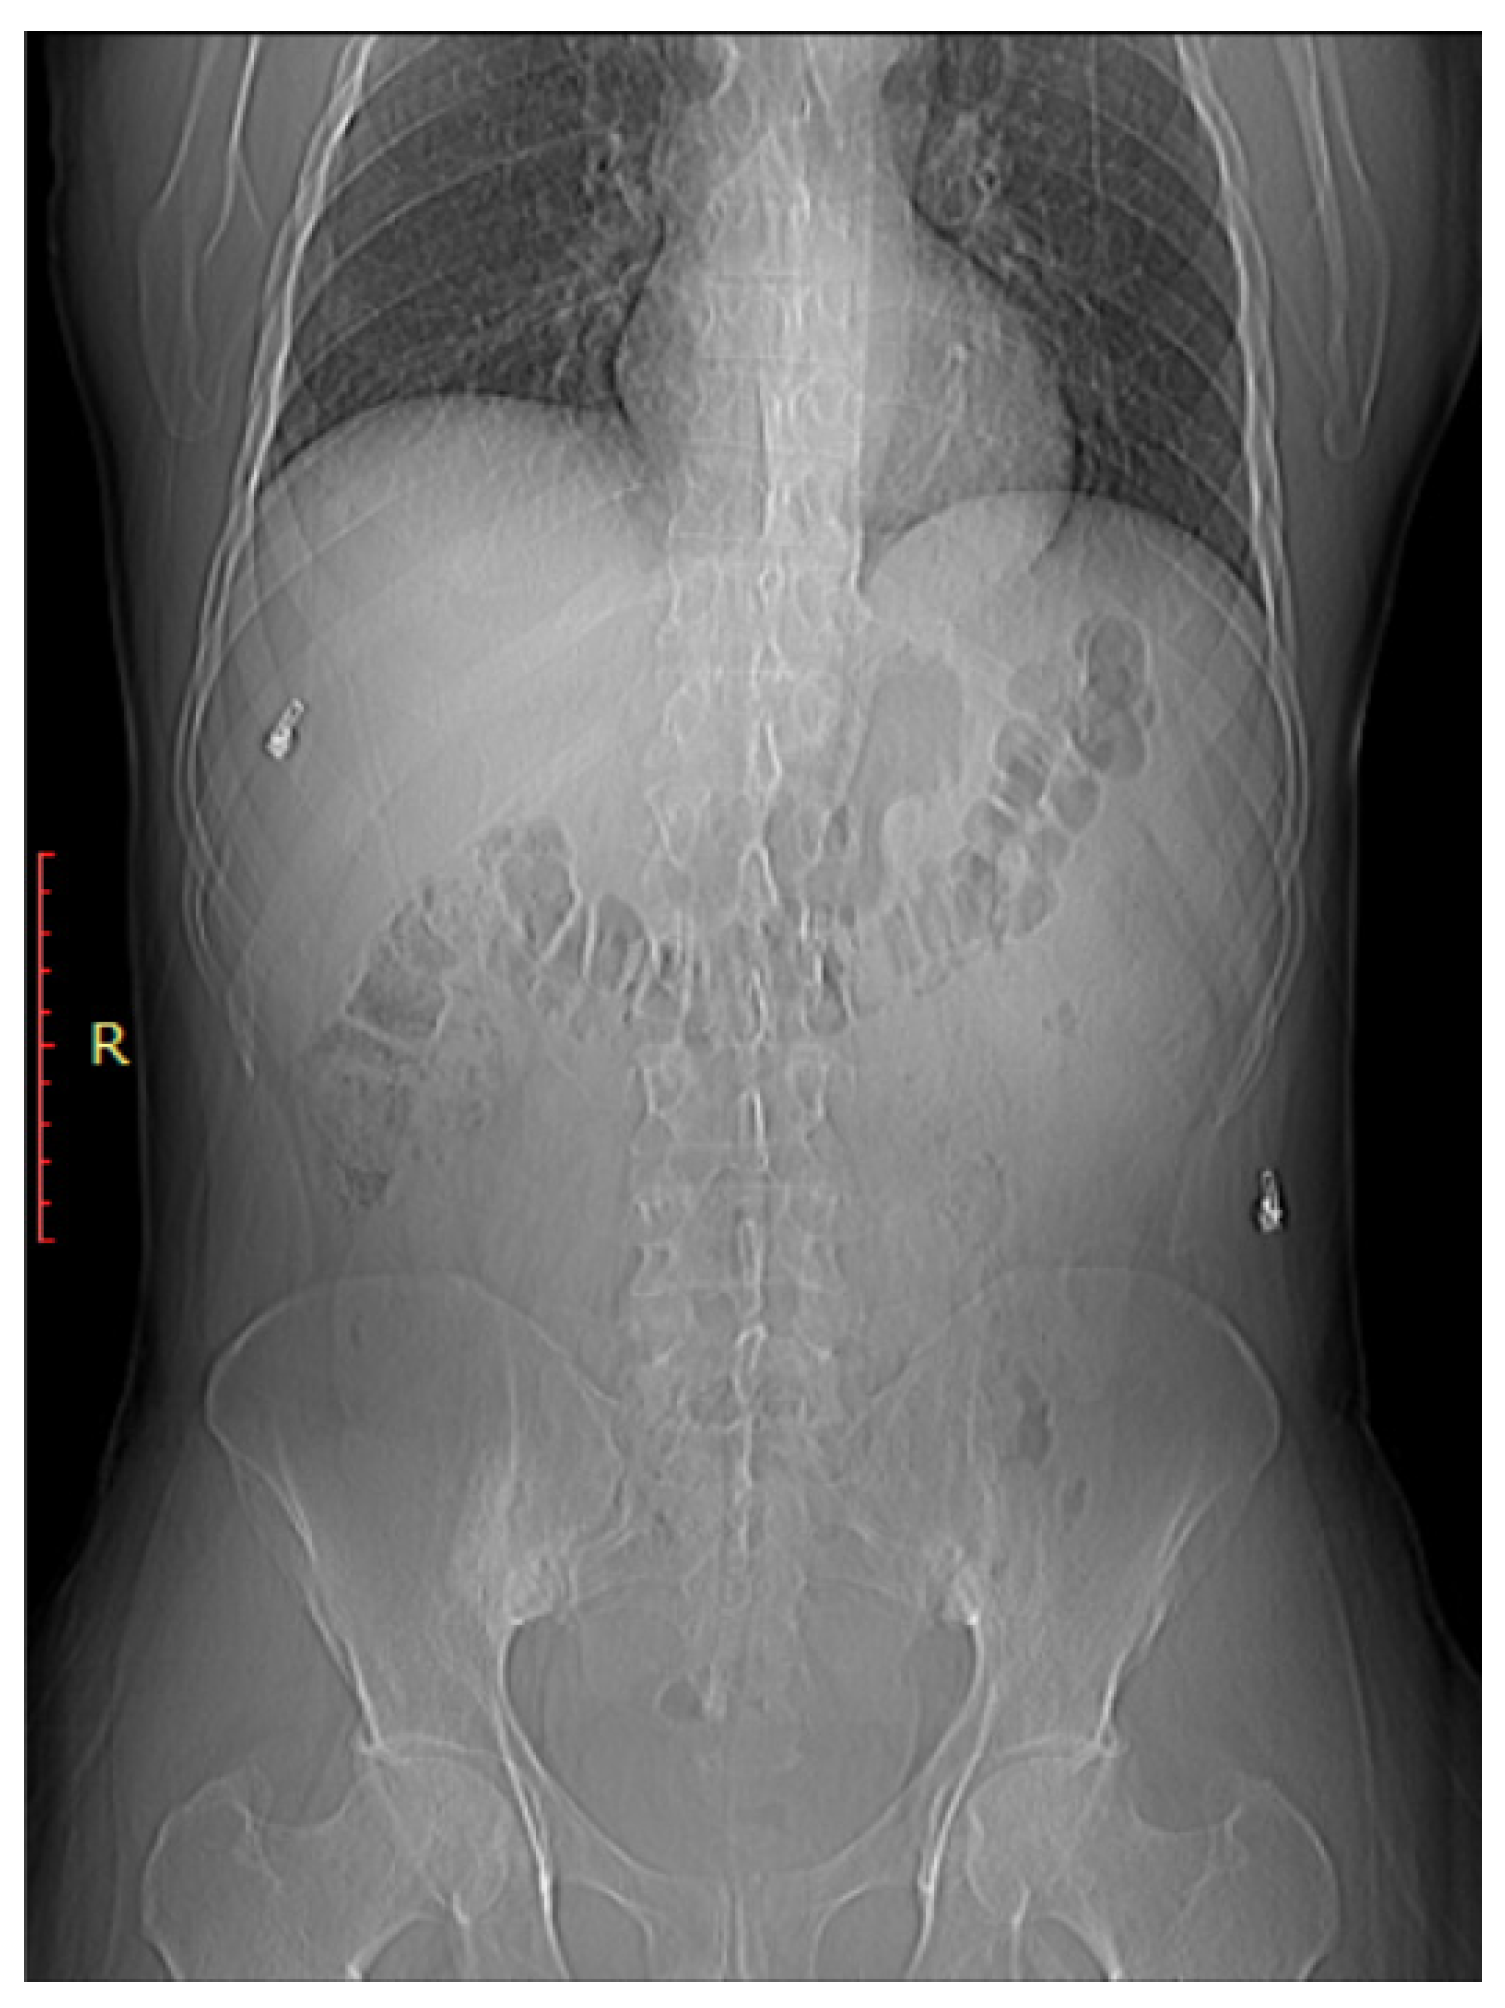

CT scans provide more detailed images of the sacroiliac joint and can reveal erosions, sclerosis, and joint space narrowing with greater clarity than X-rays [13]. Severe sacroiliitis, particularly in cases of ankylosing spondylitis, can lead to complete fusion or ankylosis of the sacroiliac joint [4]. CT scans can demonstrate the fusion as a solid, bony bridge between the sacrum and ilium [4]. CT scans can also assess soft tissues surrounding the SIJ, such as ligaments, tendons, and muscles, which may be inflamed in cases of sacroiliitis [44] as demonstrated in Figure 4 and Figure 5.

Figure 4.

Axial bone window CT scan (A) and coronal bone window CT scan (B) for a 41-year-old male presenting with Rt sciatica suggestive of bilateral sacroiliitis (same Patient as in Figure 3).